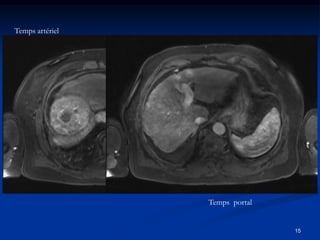

Temps artériel

Temps portal

Diagnostic non invasif du CHC sur foie de cirrhose

• Nodule < 1cm

surveillance rapprochée à 3 mois

•   Nodule entre 1 et 2 cms

*CHC si caractéristique sur 2 examens dynamiques

(TDM, IRM, Echo contraste)

hypervasculaire + « washout »portal

*si non caractéristique : biopsie

•   Nodule > 2 cms

*CHC si caractéristique sur 1 examen dynamique ou

si αFP > 200